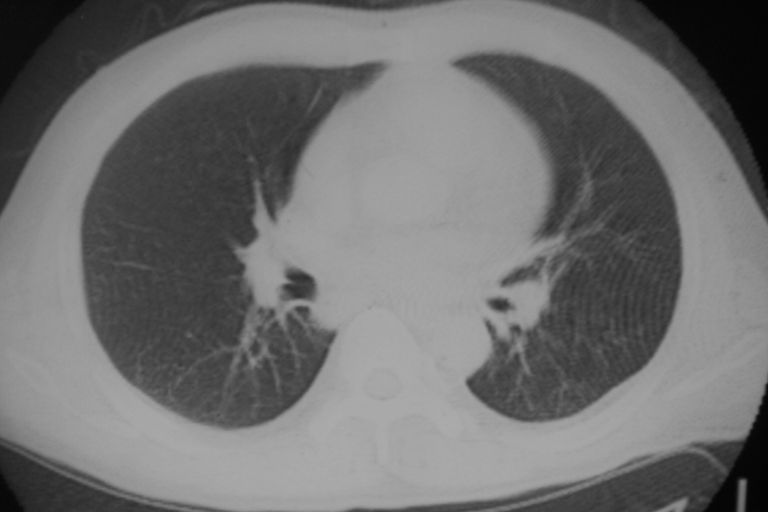

患者 男 50岁 无痛性咯血3天,无其他不适.

左下肺结节状软组织密度影,边缘有毛刺,考虑周围型肺癌。

1 左肺下叶基底段见两结节软组织密度灶, 肺窗边缘见有毛刺征像, 不能排除占位. 2 建议结合临床治疗一周后ct随访在看其结果.

左下肺基底段两个小结节影,边缘毛糙,建议抗炎治疗后复查。

临近胸膜增厚,病变周围肺不清,稍有分叶。结节密度略高,肺、纵隔窗差异不大,肺癌待排。前方还有一个

1 左肺下叶后基底段见结节软组织密度灶,建议抗炎后复查,排除肿瘤

1 左肺下叶后基底段见结节软组织密度灶,周围见毛刺,建议抗炎后复查,警惕周围型肺癌。

左下肺结节状软组织密度影,一个边缘有卫星病灶,邻近胸膜增厚.另一个有毛刺.心影周围水样密度影环绕.考虑:

1.肺癌可能.肺tb待排.

2.左侧胸膜增厚.心包积液.